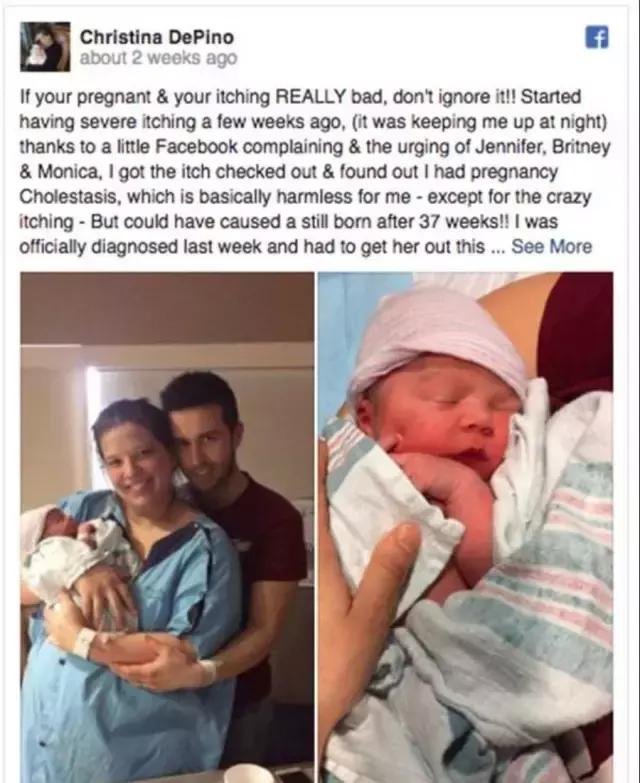

这位妈妈孕期身上奇痒,于是在社交上哭诉一番。

她的一位护士朋友看了,赶紧让她去检查。

结果居然是一种叫妊娠期肝内胆汁淤积的重病。

若不是及时发现,恐怕孩子就没了!

严重的妊娠期肝内胆汁淤积

但如果孕晚期发生难以忍受的皮肤瘙痒时,有可能是前文说到的妊娠期肝内胆汁淤积(ICP)。

这是一种只会在怀孕发生的肝脏疾病。一般发生在孕中晚期,非常容易导致死胎。

这种瘙痒一般先从手掌和脚掌开始,然后逐渐向肢体近端延伸,甚至可发展到面部。瘙痒症状短则三月长达数月。

此外,还有伴随尿色暗、排便轻度着色、疲劳、食欲不振等症状。

如果发现这种情况,要及时就医,检查。